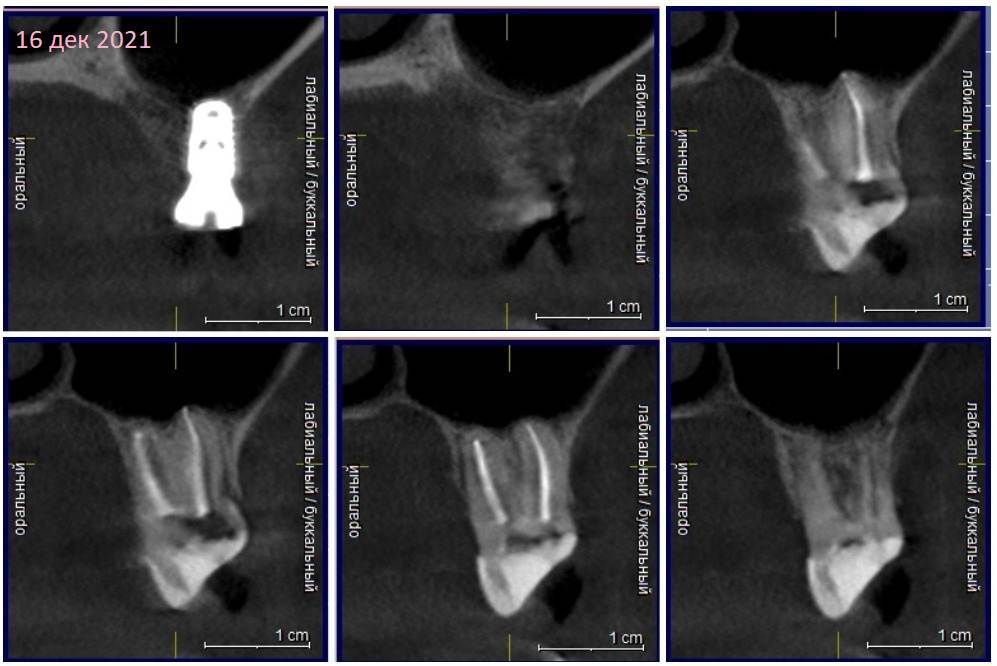

Зуб 17.

Сентябрь 2021 – удалили 16й с одномоментной имплантацией и подсыпкой кости, сразу поставили формирователь.

17 сейчас – постоянная ноющая боль разной интенсивности, иногда просыпаюсь от нее ночью. Боль при накусывании и если просто дотронуться до зуба. Периодически болит и как бы жжет в районе 16, где стоит имплант. Сильнее – после физ нагрузки.

Недавно с ужасом обнаружила, что 17 сместился в сторону импланта 16, уткнувшись в формирователь(

КТ наскринила парочку. Если нужно будет более подробно – выложу еще.

302205257_3162021.thumb.jpg.18a720cc1985f835a447cc570076ff9a.jpg

409358705_1620212.thumb.jpg.217d1a7f90d9ddcd10fa9fa074c4e53f.jpg

1663100281_1620211.jpg.bf12cf24a1038fe62444cbec72388c0a.jpg

230110228_1620213.thumb.jpg.2a516e39278fed762fb4f254cd64fd77.jpg